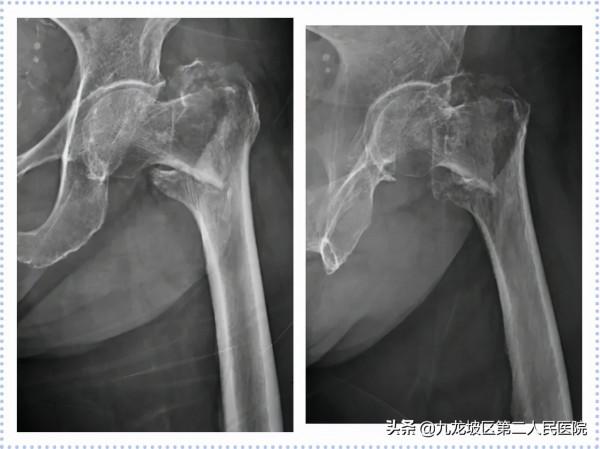

82歲女性,因“不慎摔倒致左髖部疼痛伴功能受限1天”入院。診斷為“左股骨頸骨折(GardenⅣ型)”。2021年02月26日在我院骨科行左半髖關節置換術。術後第4天扶助行器下地行走。